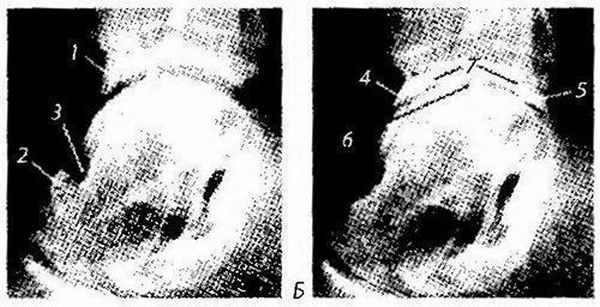

Таранно-болъшеберцовый экзостоз (рис. 344, А) — формирование костного выроста па месте ирритативного травматического раздражения области перед-ненижней границы болынеберцовой кости или бороздки шейки таранной кости (в норме место контакта указанных костей при переразгибании столы). Реже экзостоз локализуется в области внутренней или наружной лодыжки в результате прямого контакта с таранной костью при растяжении связок голеностопного сустава.

При рентгенологическом исследовании виден костный выступ в типичном месте, дегенеративных изменений не определяется (в отличие от остеофита при артрозе), линия суставной щели не изменена.

Рис. 344. Рентгенограмма голеностопного сустава с признаками таранно-большеберцового экзостоза и артроза:

А: 7 — большеберцовый экзостоз; 2 — экзостоз бороздки шейки таранной кости; 3 — бороздка шейки таранной кости; Б — проявления артроза: 4-5 — остеофиты переднего и заднего края суставной поверхности эпифиза большеберцовой кости; 6 — сужение и деформация суставной щели; 7— субхондральный склероз